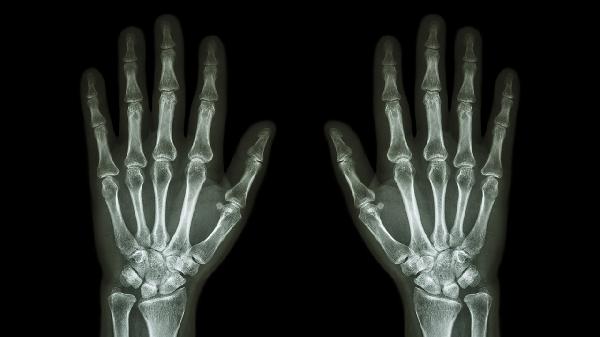

中指关节肿大变形了怎么回事

中指关节肿大变形可能由骨关节炎、类风湿关节炎、痛风性关节炎、外伤性损伤、银屑病关节炎等原因引起,可通过药物治疗、物理治疗、手术治疗等方式改善。中指关节肿大变形通常表现为关节疼痛、活动受限、晨僵、皮肤发红发热、关节畸形等症状。